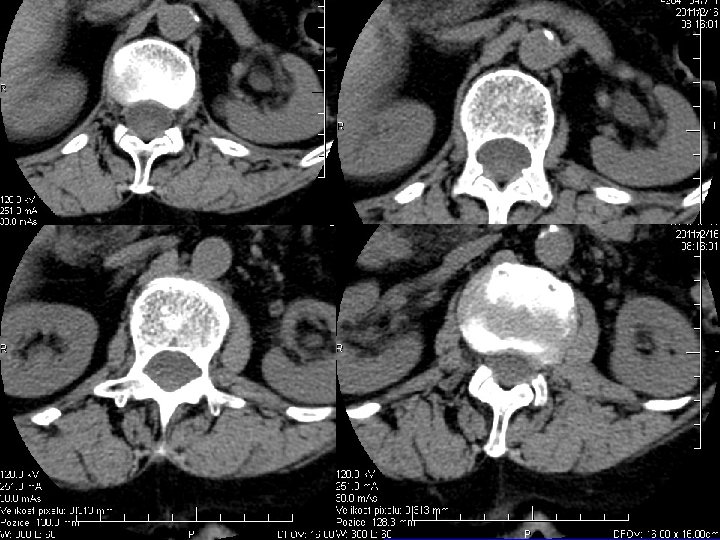

Výpočetní tomografie CT Absorpce RTG záření ve tkáních Fotony se přěměňují na el. impulsy Ty se převádí do digitální podoby Tkáňová denzita – odstíny šedi Vzduch – 1000 H. U. Voda 0 H. U. Kost + 1000 H. U. Kontrastní látky- enhancement Onemocnění kostí Nádory kostí a kloubů

CT